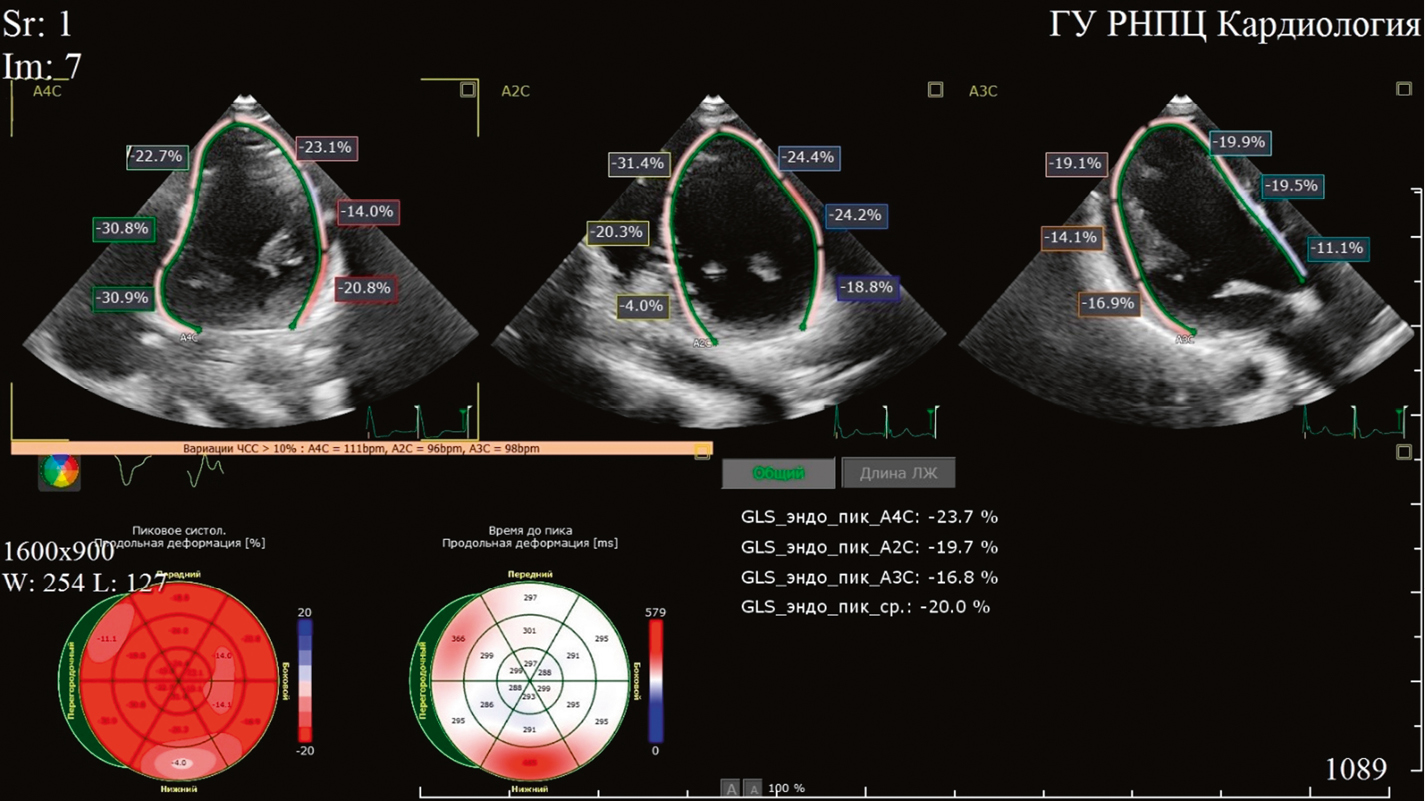

Принимая во внимание клиническую картину заболевания, результаты лабораторно-инструментальных исследований, пациентку повторно госпитализировали в кардиологическое отделение в сентябре 2024 г. для выполнения ЭЭФИ и определения дальнейшей тактики ведения. По данным ЭхоКГ, определена ФВ ЛЖ 56%, гипокинез базального передне-перегородочного и базального перегородочного сегментов ЛЖ; полости сердца не расширены. При выполнении 2D-Strain ЭхоКГ не выявлено снижения глобальной продольной деформации ЛЖ (GLS — –20,0%) (риc. 4). По данным ЭЭФИ, зафиксировано удлинение интервала HV — 86 мс (рис. 5).

Рис. 4. 2D-Strain эхокардиография пациентки К. Глобальная продольная деформация левого желудочка –20,0%.